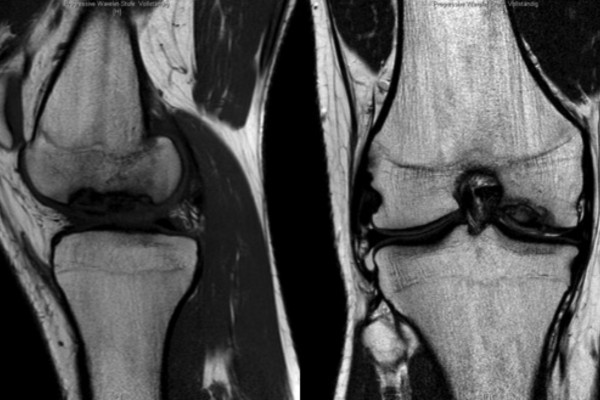

Auffüllung des entstandenen Defektes mittels Knorpel-Knochentransfer